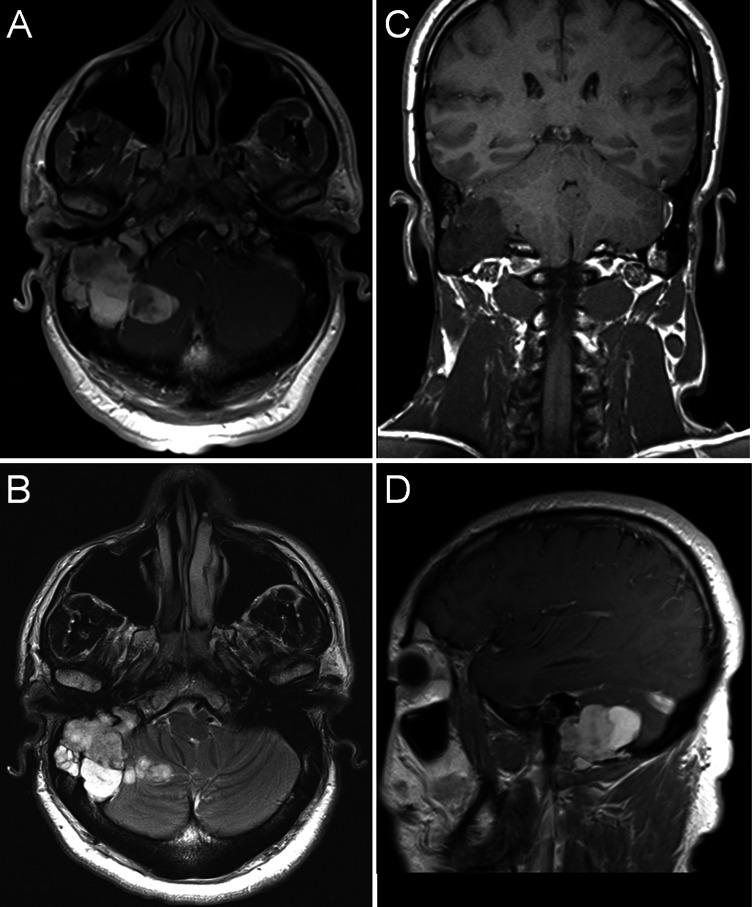

Pleomorphic adenoma, also known as benign mixed tumor, is the most common tumor affecting the parotid gland and can reach massive size; however, intracranial invasion is rare. Recurrence of pleomorphic adenoma after excision is a well-known phenomenon and can present decades after resection of the primary tumor. Here we present the case of a 53-year-old man who presented to our clinic with ear fullness, otalgia, and hearing loss 30 years after undergoing total parotidectomy and external beam radiotherapy for pleomorphic adenoma. Magnetic resonance imaging revealed a massive transcranial tumor invading the mastoid cavity, the dura of the posterior fossa, the fallopian and semicircular canals, the jugular foramen, the lateral infratemporal fossa skull base, the sigmoid and transverse sinuses, and the superior parapharyngeal region. Gross examination and histopathological studies confirmed that the mass was a recurrent pleomorphic adenoma. Here we discuss the features of recurrent pleomorphic adenoma and review the current literature.

多形性腺瘤,也称为良性混合瘤,是最常见的累及腮腺的肿瘤,可长得很大;然而,颅内侵犯很少见。多形性腺瘤切除术后复发是一种众所周知的现象,可在原发肿瘤切除数十年后出现。在此我们报告一例53岁男性患者,他在因多形性腺瘤接受全腮腺切除和外照射放疗30年后,因耳部胀满、耳痛和听力减退前来我院就诊。磁共振成像显示一个巨大的经颅肿瘤,侵犯乳突腔、后颅窝硬脑膜、面神经管和半规管、颈静脉孔、颞下窝外侧颅底、乙状窦和横窦以及咽旁间隙上部。大体检查和组织病理学研究证实该肿块为复发性多形性腺瘤。在此我们讨论复发性多形性腺瘤的特征并回顾当前文献。